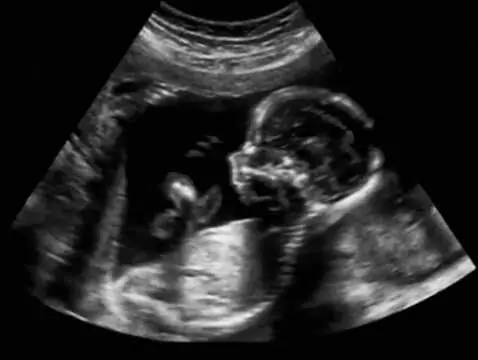

Badania prenatalne przeprowadzane w I i II trymestrze ciąży pozwalają na wykrycie wielu wad u rozwijającego się dziecka. Nieinwazyjne badania prenatalne są bezpieczne zarówno dla matki, jak i...